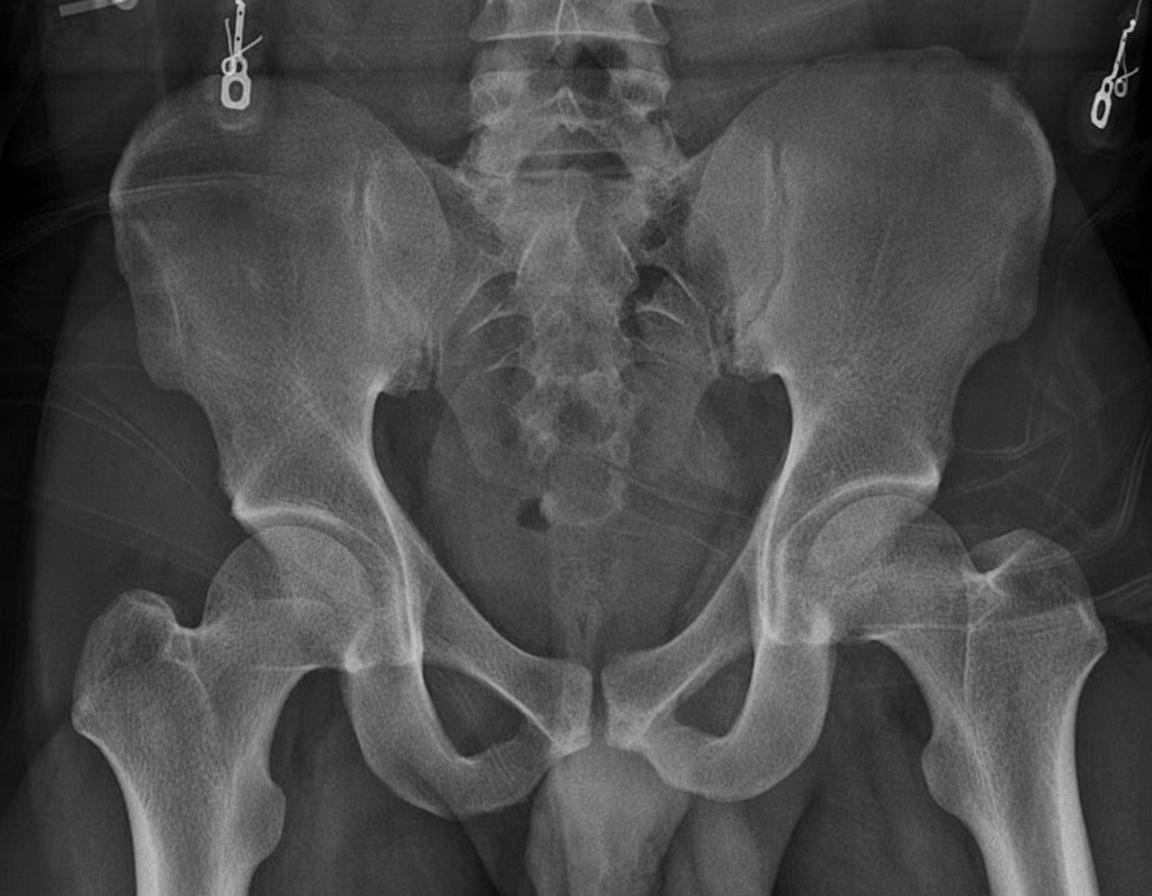

The following Pelvic Radiograph is seen in which condition?

Explanation: ***Nail Patella Syndrome*** - Characterized by **pathognomonic iliac horns** - bilateral bony projections from the posterior iliac crests visible on AP pelvic radiographs. - This **hereditary osteo-onychodysplasia** presents with distinctive skeletal abnormalities including patellar hypoplasia and elbow dysplasia. *Achondroplasia* - Shows **narrowing of interpedicular distance** in the lumbar spine and **champagne glass pelvis** configuration. - **Iliac horns are not present** - instead demonstrates broad, flared iliac wings with horizontal acetabular roofs. *Osteoarthritis* - Presents with **joint space narrowing**, **osteophytes**, and **subchondral sclerosis** affecting weight-bearing joints. - **No iliac horn formation** - changes are limited to articular surfaces and periarticular bone formation. *Rheumatoid Arthritis* - Shows **symmetric joint erosions** and **osteopenia** with possible **protrusio acetabuli** in advanced cases. - **Absence of iliac horns** - inflammatory changes affect synovial joints without producing bony projections from iliac crests.